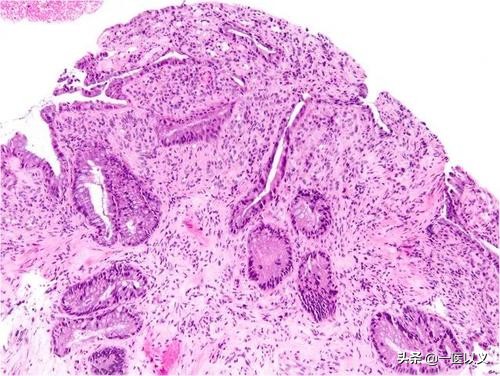

3、患者进行结肠镜检查时, 会发现肠道粘膜有明显的水肿、充血表现 ,如果病情严重的话,还可能出现肠道的溃疡。

2、进行结肠镜检是诊断克罗恩定的主要手段之一,因为在肠镜下可以看到患者肠壁出现阶段性炎症,此外,还有裂隙性溃疡表现。